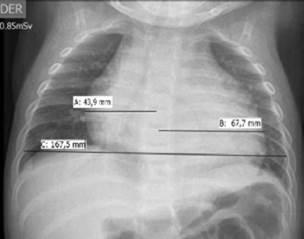

On admission, the patient presented: heart rate of 186 beats per minute; no hypotension (blood pressure at 106/65 mmHg); respiratory frequency of 50 breaths per minute; fever (38.3°C); SaO2 in 74% with oxygen at one liter per minute; mucocutaneous pallor; somnolence; no jugular vein engorgement; audible, rhythmic and tachycardic heart sounds; no pericardial rub, rhonchi and crepitus in both lungs; subcostal and suprasternal retractions; no hepatomegaly or edema; peripheral pulses and capillary refill without alterations, which required increased oxygen delivery (FIO2 0.5). His hemogram showed leukocytosis of 30 230mm3 with polymorphonuclear leukocytes of 24 360mm3, thrombocytosis (platelets of 1 006 000mm3); 5.8g/d serum proteins, and increase in acute phase reactants: C reactive protein of 96mg/L and procalcitonin of 5.24ng/ mL. Initial chest X-ray showed cardiomegaly, bibasilar and retrocardiac parenchymal opacities, without signs of pulmonary congestion or pleural effusion (Figure 1).

Initial chest x-ray.

Figure 1: Initial chest x-ray.

Source: Own elaboration based on the data obtained in the study.

The initial chest X-ray showed bibasilar and retrocardiac consolidations. The cardio-thoracic index was 0.66 (>0.55) and was interpreted as cardiomegaly considering the patient's age. There was no evidence of pulmonary hyperflow or pulmonary venous congestion. The latter, together with electrocardiographic alterations (repolarization disorders compatible with acute pericarditis) and absence of signs of heart failure (no signs of systemic or pulmonary congestion or low cardiac output), led to rule out pericarditis and associated pericardial effusion, without cardiac tamponade at first. 3,12